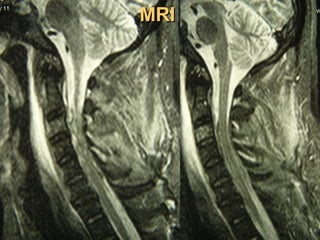

MRIMRI